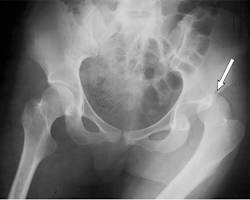

• Hip: Hip dislocations are also less common but can be life-threatening if not treated promptly.